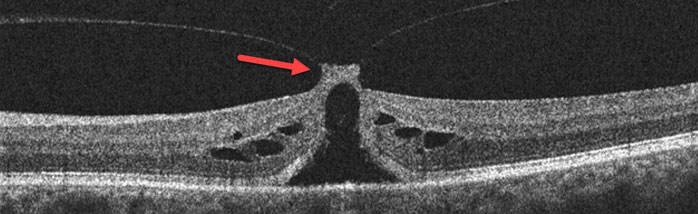

Throughout life the vitreous (the gel-like substance inside the eye) normally liquefies and gradually separates from the retinal surface. Although this usually results in a complete separation of the vitreous (posterior vitreous detachment), it can sometimes remain stuck to the central macula, the specialized area of the retina that gives us our straight-ahead reading and driving vision. Vitreomacular traction occurs when the adherent vitreous tugs and distorts the macula.

The mechanical tugging on the macula causes the central vision to be blurred or distorted. In some, the traction can progress to a macular hole. Patients may be completely asymptomatic, especially when the other eye sees normally.

You can’t diagnose vitreomacular traction by looking in the mirror since your eye will look and feel normal. The diagnosis is made with a thorough retinal examination through a dilated pupil and confirmed with OCT scanning.